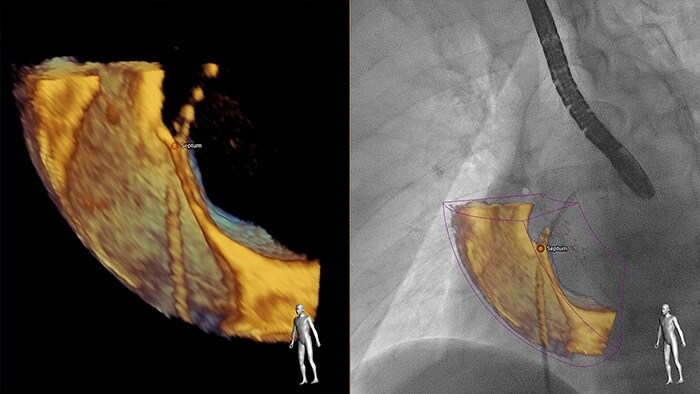

Meer inzicht en vertrouwen in het vinden en behandelen van het probleem door SmartFusion. EchoNavigator koppelt live 3D TEE en live röntgenbeelden automatisch in real time, zodat u uw instrument sneller intuïtief kunt geleiden in de 3D-ruimte.